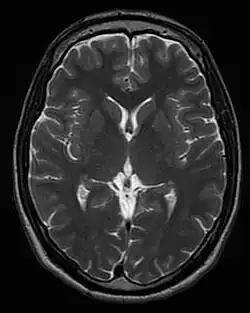

Each tissue returns to its equilibrium state after excitation by the independent relaxation processes of T1 (spin-lattice; that is, magnetization in the same direction as the static magnetic field) and T2 (spin-spin; transverse to the static magnetic field). To create a T1-weighted image, magnetization is allowed to recover before measuring the MR signal by changing the repetition time (TR). This image weighting is useful for assessing the cerebral cortex, identifying fatty tissue, characterizing focal liver lesions, and in general, obtaining morphological information, as well as for post-contrast imaging. To create a T2-weighted image, magnetization is allowed to decay before measuring the MR signal by changing the echo time (TE). This image weighting is useful for detecting edema and inflammation, revealing white matter lesions, and assessing zonal anatomy in the prostate and uterus.

The information from MRI scans comes in the form of image contrasts based on differences in the rate of relaxation of nuclear spins following their perturbation by an oscillating magnetic field (in the form of radiofrequency pulses through the sample).[19] The relaxation rates are a measure of the time it takes for a signal to decay back to an equilibrium state from either the longitudinal or transverse plane.